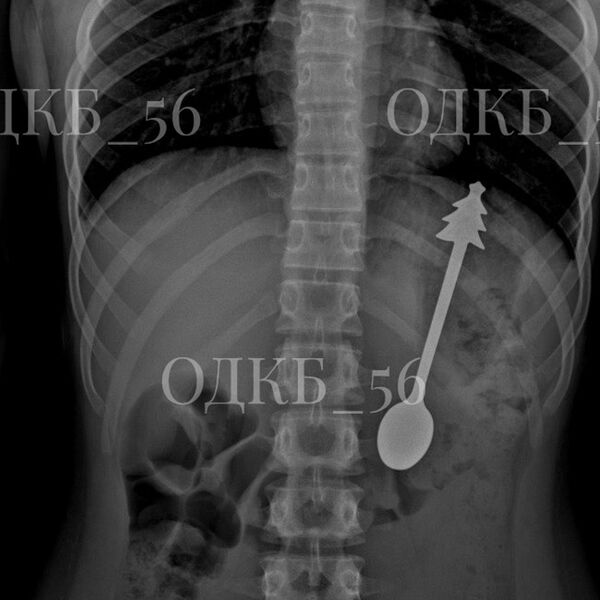

Врачи извлекли 14-сантиметровую ложку из желудка ребенка в Оренбургской области. Об этом сообщила пресс-служба регионального министерства здравоохранения на странице в социальной сети «ВКонтакте».

По данным ведомства, несовершеннолетний случайно проглотил ложку, после чего его срочно госпитализировали. Бригада скорой помощи доставила ребенка в детскую больницу, где ему сделали рентген органов брюшной полости. В результате выяснилось, что инородное тело находится в желудке.

«В экстренном порядке проведено <...> эндоскопическое удаление инородного предмета — металлической ложки длиной 14 см. Постманипуляционный период протекал без осложнений», — говорится в заявлении.

Публикация дополнена фотографиями извлеченной из ребенка ложки. На кадрах видно, что на конце ручки столового прибора находится фигурка елки.